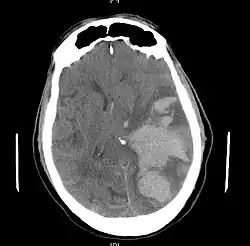

![]() Obraz TK wgłobienia podsierpowego. | |